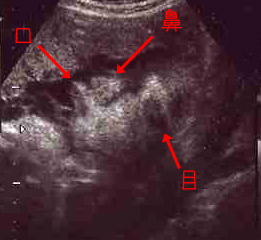

せまそうだー!

<クリックで拡大>

もう、顔が半分しか映ってないやん^^

36W1D

★頭の大きさ(横幅)8.91センチ

★体重 2648グラム